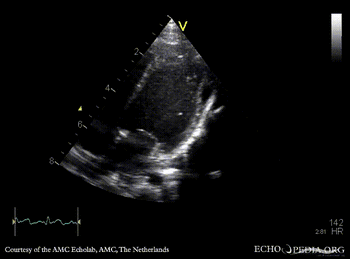

| Courtesy of: AMC Echolab, AMC, The Netherlands | |

| A4CH: pericardcyst | A4CH: pericardcyst, dimensions |